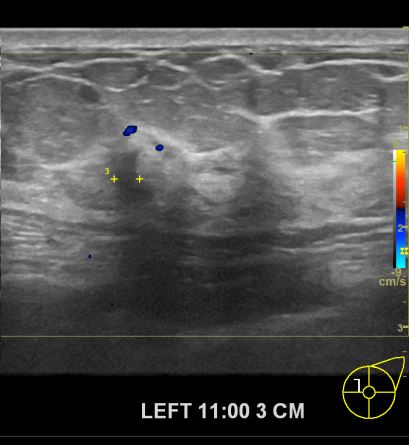

건강검진상 이상 소견으로 내원한 60대 여성분으로 초음파진료이후

의심스러운 좌측유방의 혹을 조직검사 시행후 유방암진단 되셨읍니다